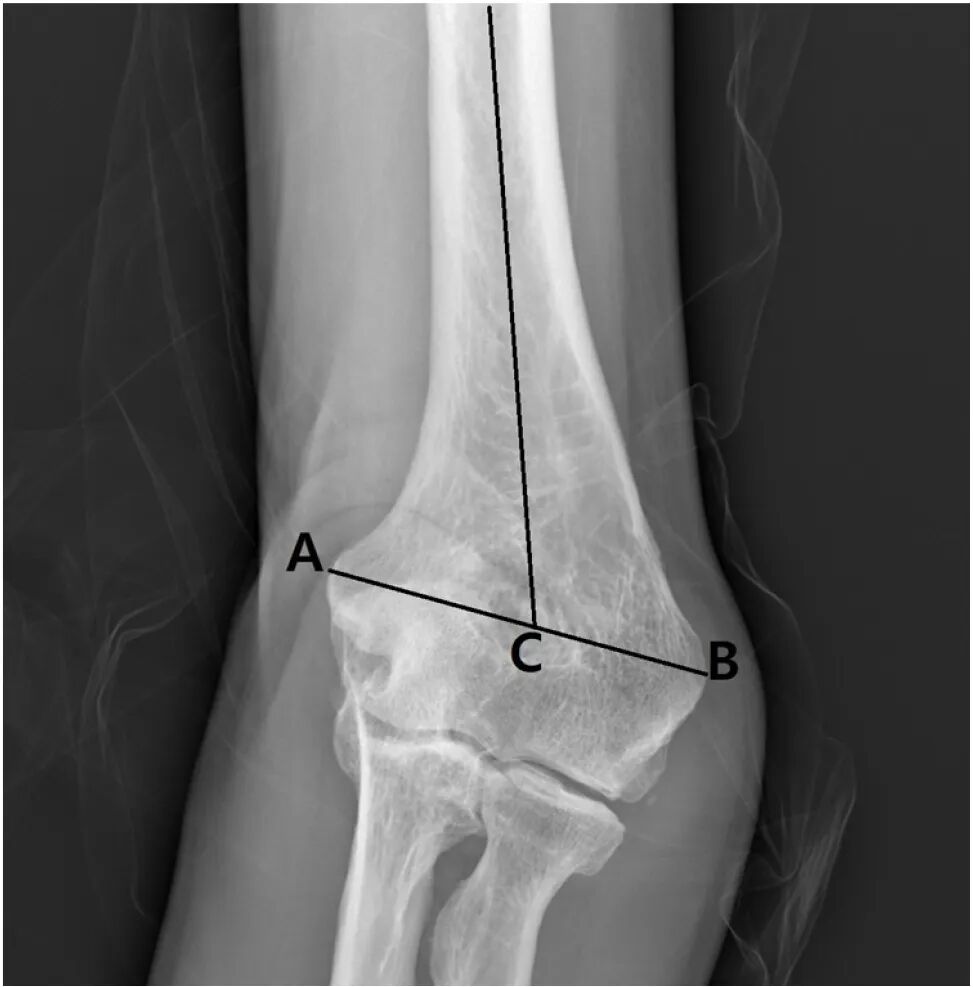

此外,为了评估肱骨本身的畸形,测量并比较了肱骨远端携带角(DHCA)。DHCA 定义为肱骨滑车与肱骨小头连线与肱骨轴线之间的夹角

图片

肱骨远端携带角,定义为连接肱骨滑车和肱骨小头的线与肱骨轴线之间形成的角度。